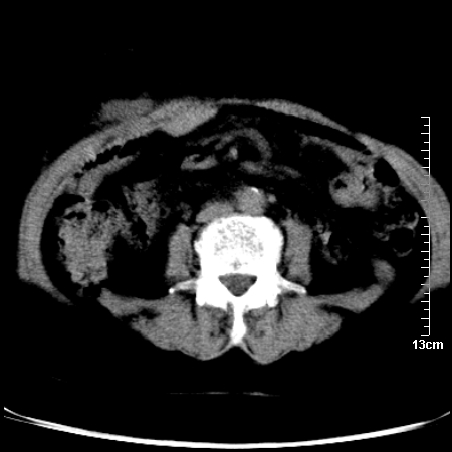

术前的疏忽,手术前诊断阑尾炎,但是没有常规做b超,导致术后1周检查发现 1。实性包块?2。腹腔术后脓肿?

病史:病人一周前诊断阑尾炎,未做b超,手术发现阑尾化脓,(没有留意有无包块),术后1周病人发热,血象:1.6万,做b超发现,随ct检查,上传图片

巨大囊实性包块,边界大部尚清楚,不太像脓肿的表现。应该做个增强检查除外盆腔肿瘤。

脓肿可能性大. 因回盲部区域化脓性兰尾切除残端感染改变征像与实性肿块关系密切.肿块上界至右下腹,下界至盆腔膀胱上缘, 如果是实性肿块在兰尾术中可能就会发现. 所以术后一周病人高烧, 白细胞增高,临床表现支持脓肿.

盆腔一边界大部份清晰囊实性肿块,其周腹脂未见确切异常,其一端与右侧附件相连。考虑右侧附件肿瘤。

如果能进行肠道准备就好了!盆腔内巨大囊实性包块,右前缘与周围肠管分界不清,病灶内前部的气体是否为肠管内气体形成的假象不能确定。

这么大一包快手术当中没有发现?值得怀疑!结合化脓性阑尾炎病史,首先考虑脓肿!不排外附件来源的肿瘤,建议增强扫描!!